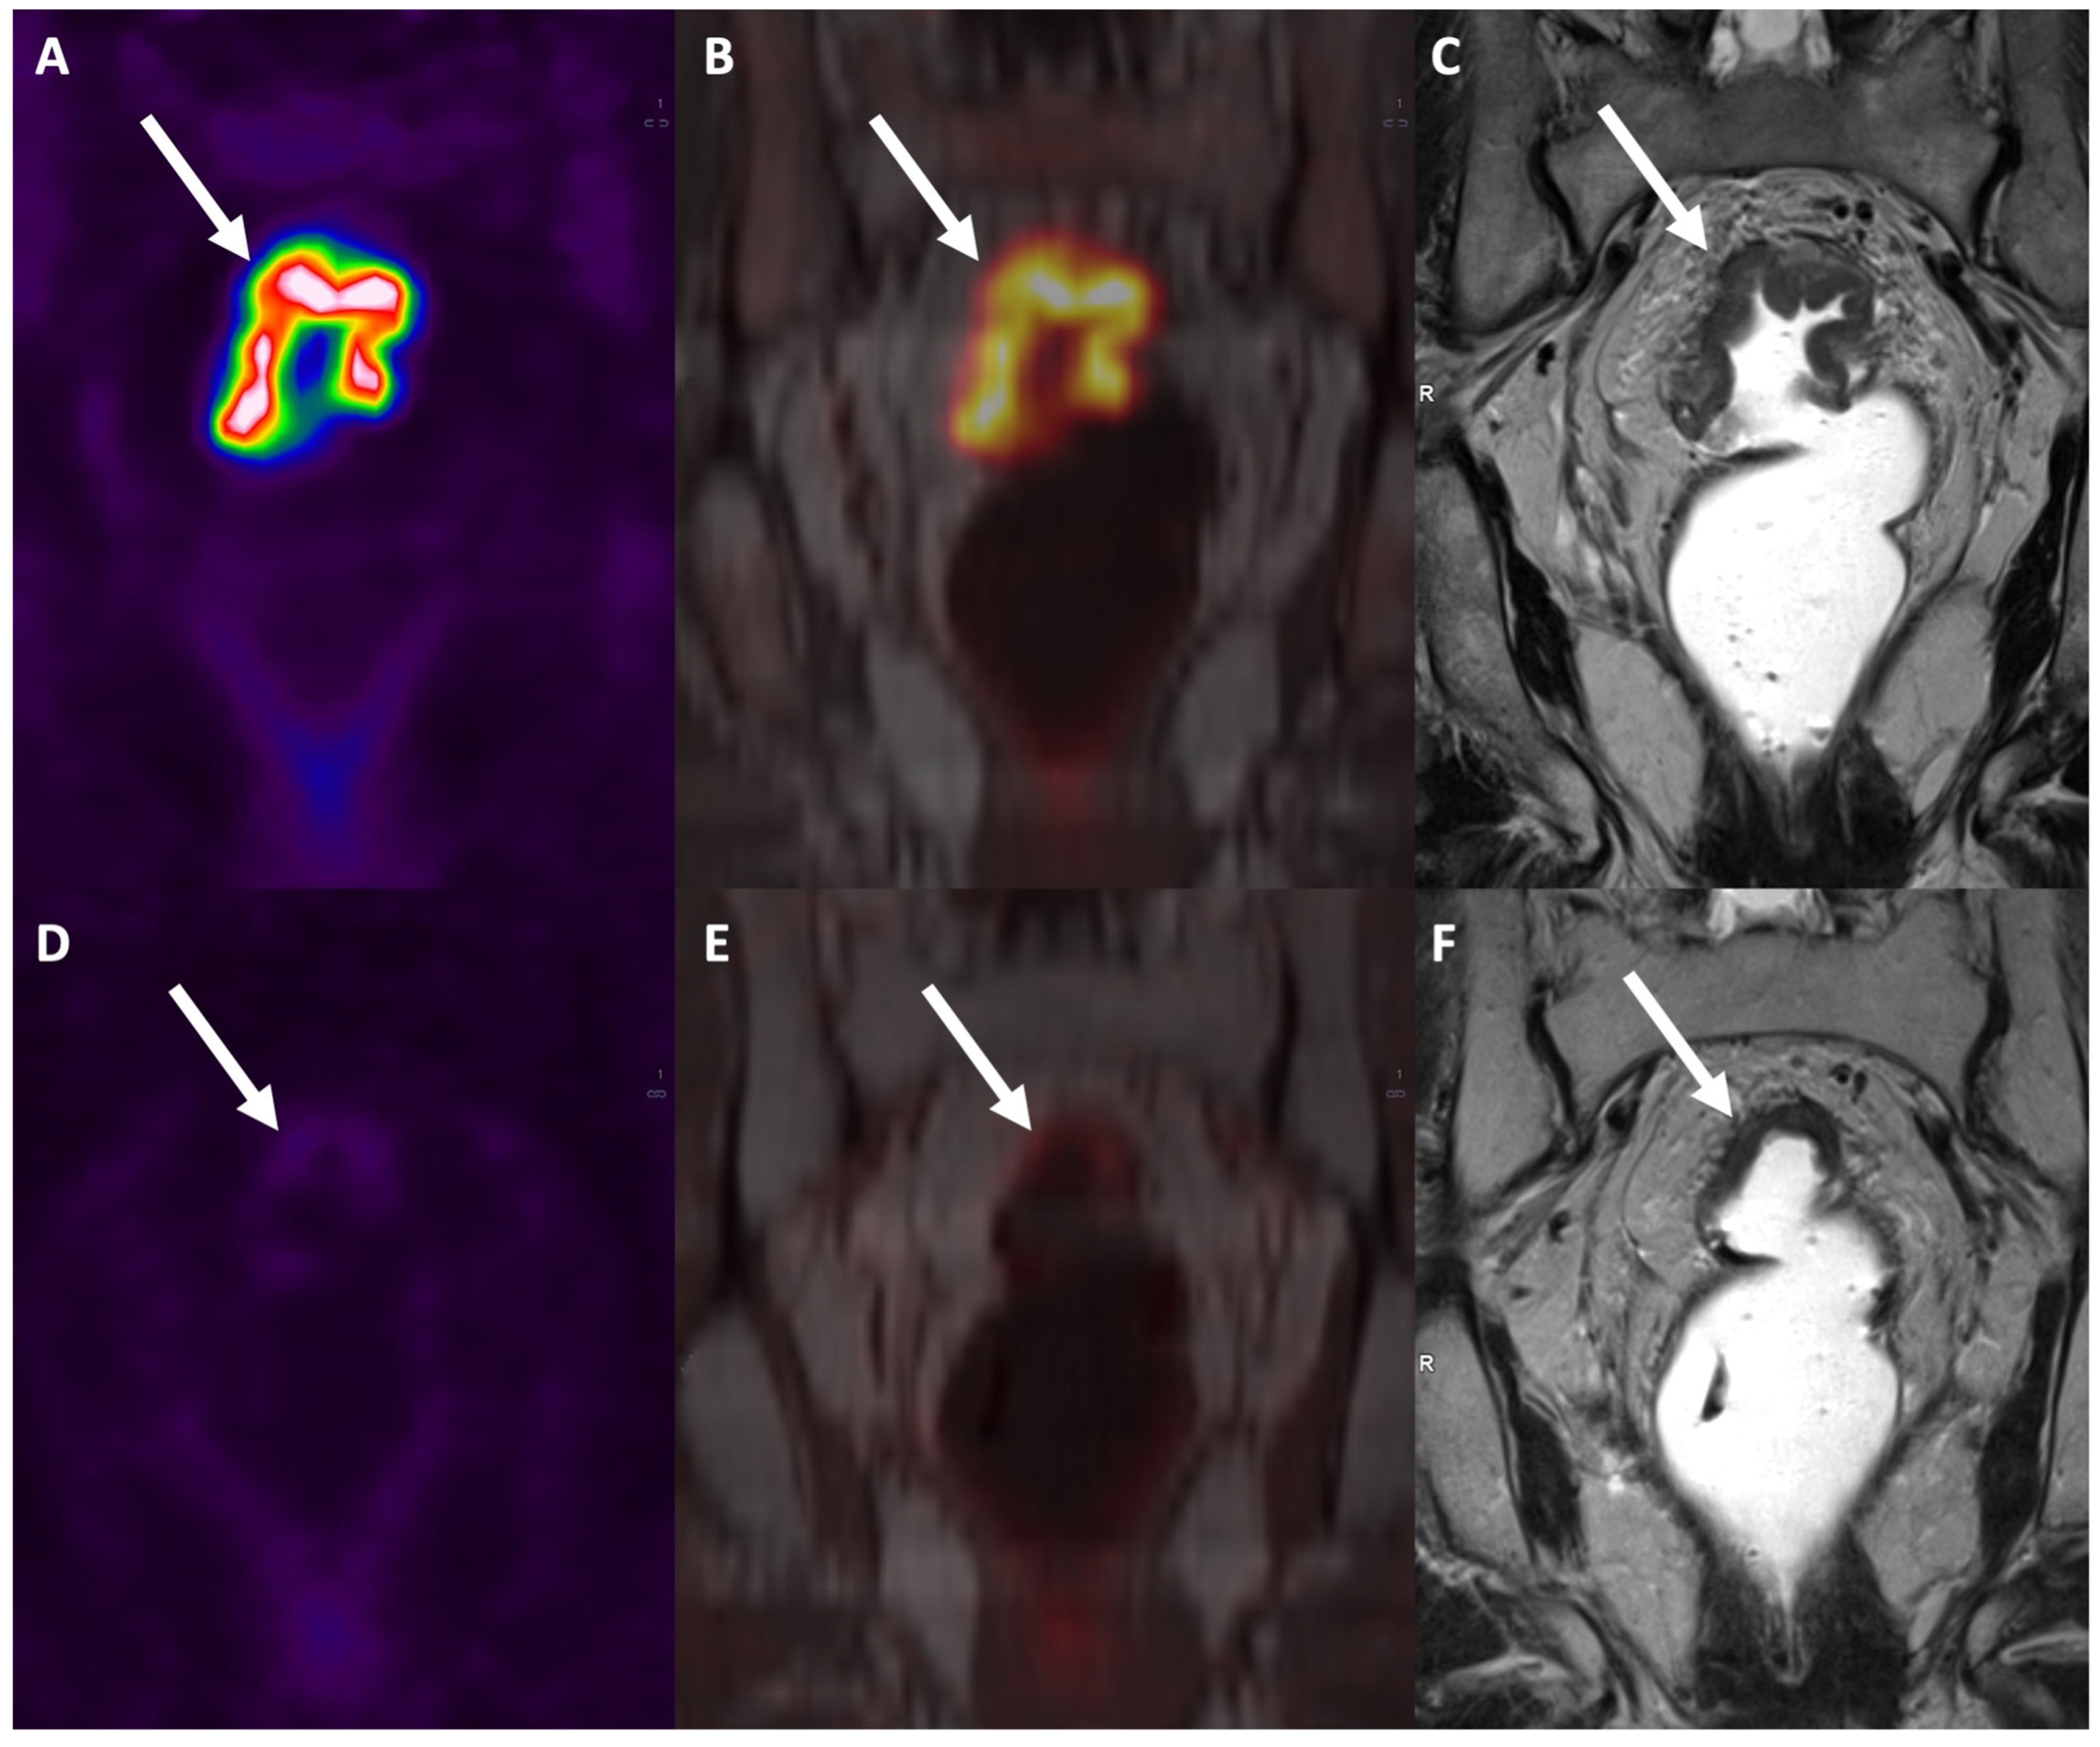

3.2. N Staging

3.3. New Techniques and Applications